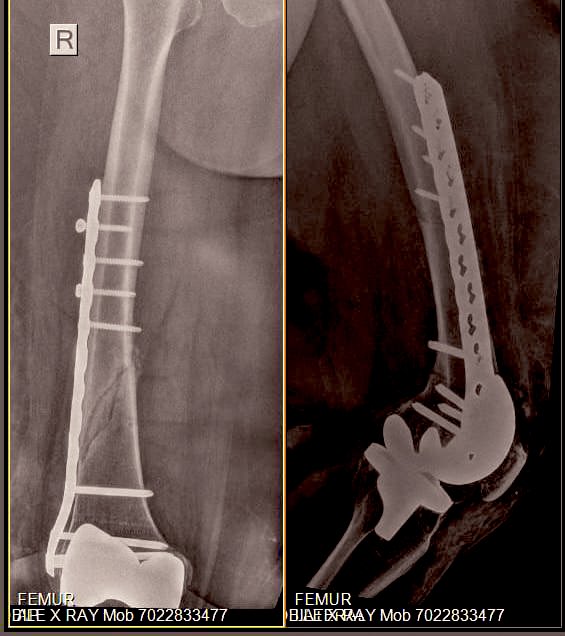

Our Joint Replacement Surgeon & Trauma Surgeon got together to plan + execute her surgery & recovery from here.

They finally decided to use β€œless invasive variable locking plate” from Synthes for her.

The end result was marvellous, with small 3 inch incision & few punctures to pass screws on proximal end of implant

However, this was post op day one & we knew she had a long way for complete recovery & rehabilitation